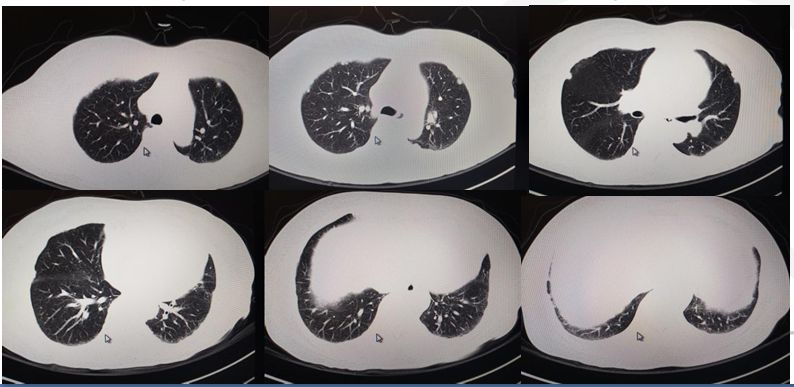

•入院后查血肿瘤标志物正常,T-SPOT阴性。胸部CT见两肺内少许絮索条影,两侧胸膜结节状增厚伴散在钙化。

影像学主要表现为胸腔积液、胸膜肿块和胸膜增厚。典型的表现为胸内弥漫性不规则胸膜增厚和突向胸膜腔内的驼峰样多发结节,呈波浪状阴影,在胸液引流后行X线检查可能发现肺部网状阴影、胸膜斑等石棉接触的证据。